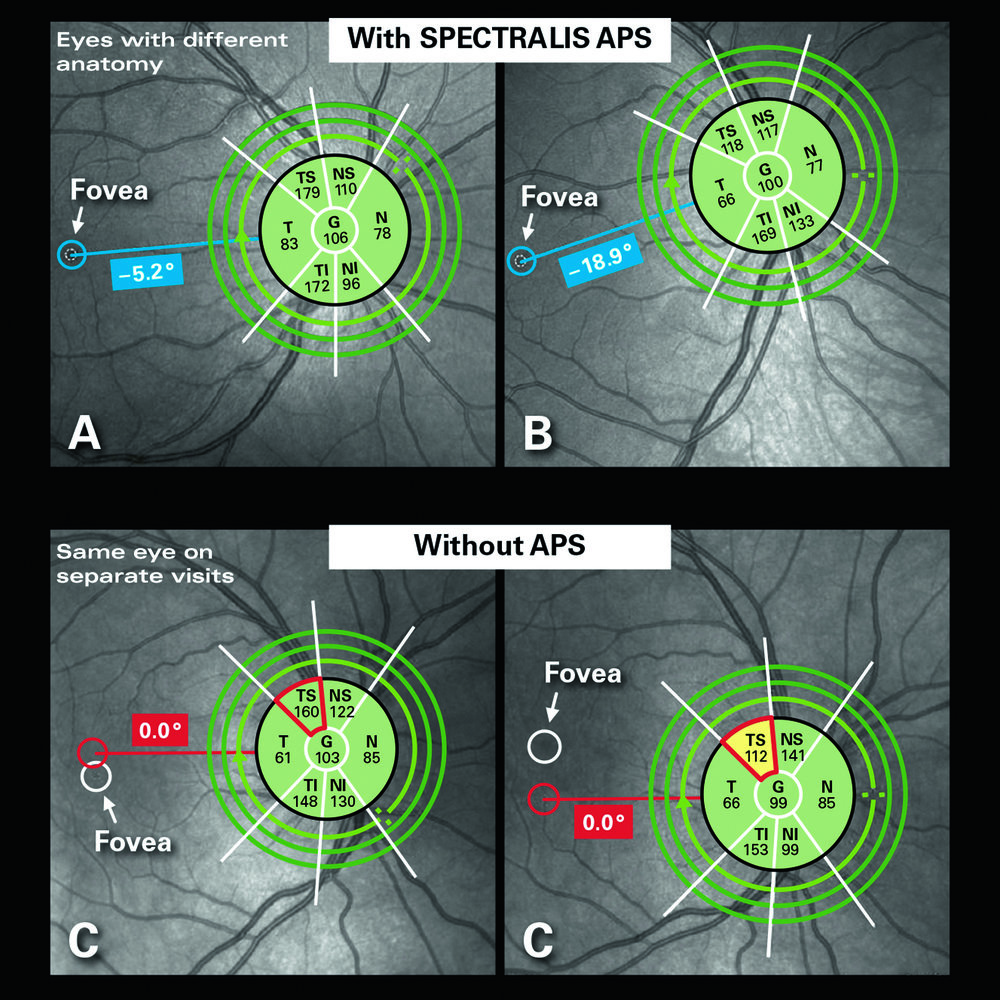

Glaucoma Module Premium Edition per Heidelberg Spectralis OCT è l’evoluzione diagnostica nel campo del glaucoma. Si tratta di un modulo opzionale applicabile su tutti i sistemi OCT basato su un concetto innovativo che rende tutte le misurazioni e la loro correlazione con database normativo oggettive e assolutamente più precise. Il modulo GMPE è dotato del sistema APS (Anatomic Positionig System), evoluzione del brevettato LiveEyeTracking (TrueTrack) di Heidelberg consente al sistema di individuare automaticamente la fovea ed il centro del nervo ottico così da allineare ogni esame alla specifica anatomia del paziente eliminando perciò tutti gli artefatti derivanti dalla correlazione con database in caso di tilting. Con la semplice esecuzione di due esami combinati il software permette di analizzare i fasci della neurorima (MRW-BMO MinimumRimWith-BruchMembrainOpening), le fibre peripapillari a tre distanze (RNFL con circle scan dedicata a tre diametri: 3,5mm-4,1mm-4,7mm) e tutto il polo posteriore sia in struttura che in asimmetria di spessore a tutti i livelli di stratificazione retinica (segmentazione a 10 strati retinici per topografia di spessore e valutazione anche del singolo strato GCL). Glacoma Module Premium Edition è anche il più valido aiuto per seguire il paziente nel tempo, sempre basato sul DNA Spectralis garantisce un riesame con mergine di errore di 1micron e genera automaticamente un grafico di progressione per ogni modalità di rielaborazione disponibile ad ulteriore completamento di un pacchetto diagnostico Premium che aggiunge un ulteriore tassello al imaging multimodale di Spectralis.